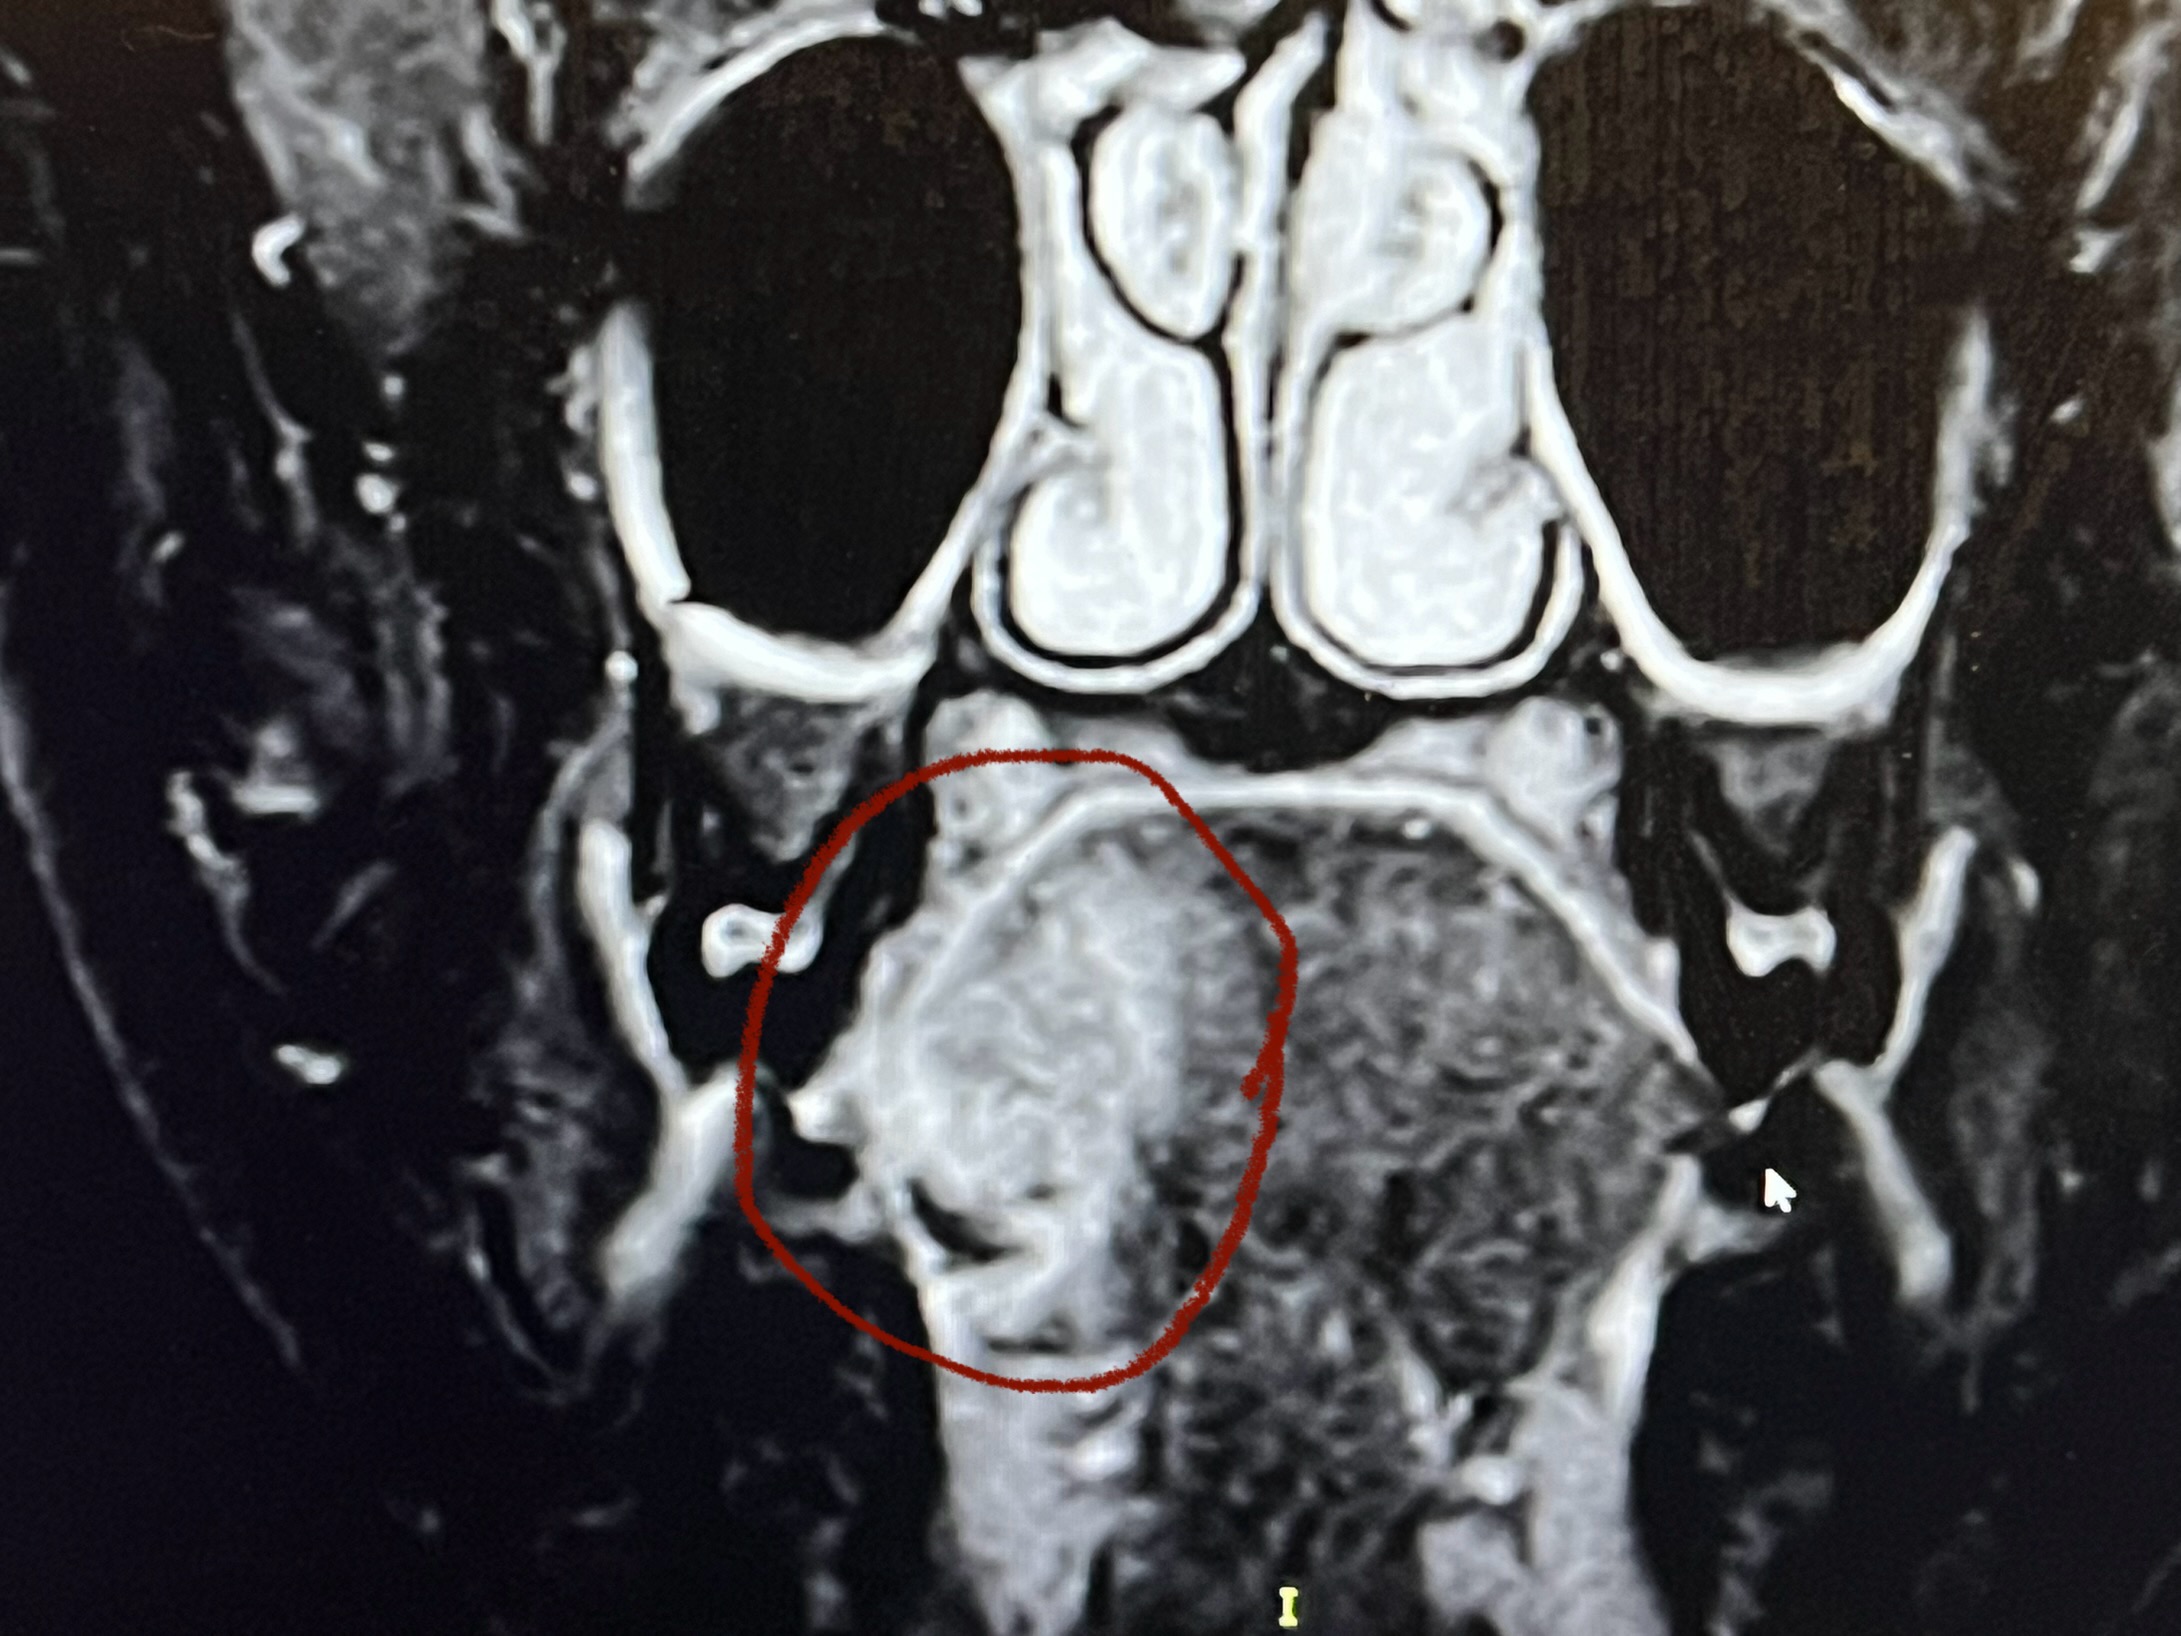

הביולוגיה של HNSCC

הבסיס הנדרש להבנת סרטן ראש-צוואר. מתחילים מהיסוד, עולה בהדרגה